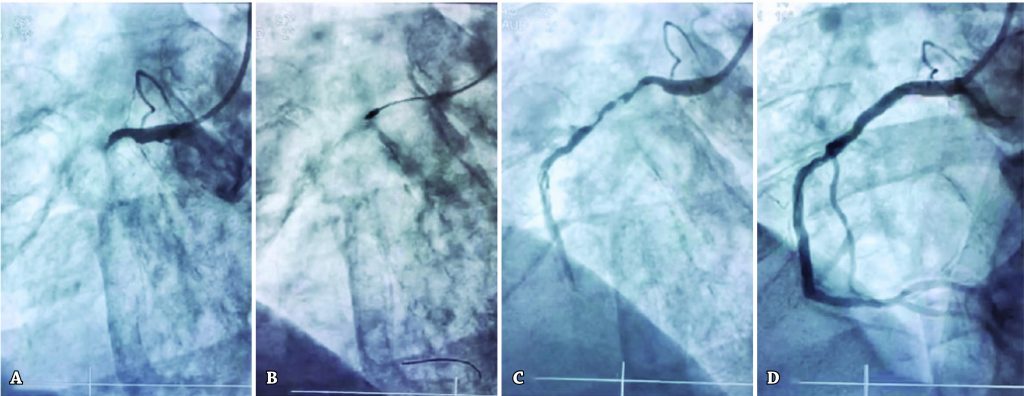

Uma coorte de 138 indivíduos foi acompanhada após aterectomia rotacional entre os anos de 2012 e 2016. Os fatores de risco mais frequentemente observados foram hipertensão (87%), dislipidemia (69%), diabetes melito (44%) e sedentarismo (72%). Foram tratados 244 vasos, dos quais 179 com auxílio de aterectomia rotacional, e implantados 308 stents farmacológicos. O escore SYNTAX II foi 22,4±11,5, com 18% dos indivíduos classificados como de alto risco (>33 pontos); acesso arterial femoral ocorreu em 76,8%. A transposição da lesão foi alcançada em 98% dos casos. O sucesso angiográfico foi obtido com o implante de stent em 98% dos procedimentos. O tempo de internação hospitalar foi de 2,6±3,7 dias. A mortalidade intra-hospitalar foi de 4%, e a mortalidade em 4 anos foi de 14,5%. O seguimento tardio foi realizado por ligações telefônicas até 4 anos após o procedimento. Dentre os pacientes, 97% mantiveram o uso regular de terapia antiplaquetária dupla. Apenas 42% relataram exercícios regulares. Angina pectoris foi relatada por 13% dos indivíduos.

A aterectomia rotacional apresentou baixa ocorrência de eventos adversos nas evoluções imediata e tardia, levando à alta taxa de sucesso do implante de stent em lesões complexas.